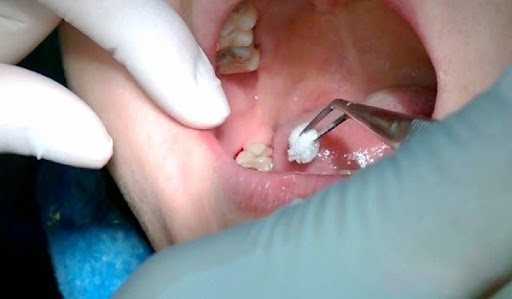

Trong một số trường hợp nhất định, bác sĩ có thể đặt thuốc hoặc ghép xương vào khe lỗ sau khi nhổ răng khôn để tạo điều kiện phục hồi tự nhiên của cơ thể. Bạn cần thực hiện tốt công tác vệ sinh để hạn chế nguy cơ nhiễm trùng sau khi nhổ răng khôn và để lại sẹo mô nướu hoặc lỗ thủng trong miệng.

- Dùng gạc chấm nhẹ nhàng lên vết thương để hút máu thừa, tránh thực hiện mạnh tay để hạn chế tình trạng lỗ sau khi nhổ răng khôn bị tổn thương và máu tiếp tục chảy.

- Cắn bông gạc: Mục đích để cầm máu tại vị trí vết thương. Bạn sẽ phải cắn trong vòng 1 giờ, nếu cắn bông lâu hơn, máu đông có thể dính vào gạc khi lấy ra và khiến máu tiếp tục chảy.

Hình ảnh sau khi nhổ răng khôn

Dưới đây là một số hình ảnh lỗ sau khi nhổ răng khôn của bạn tại Nha Khoa Miền Tây: